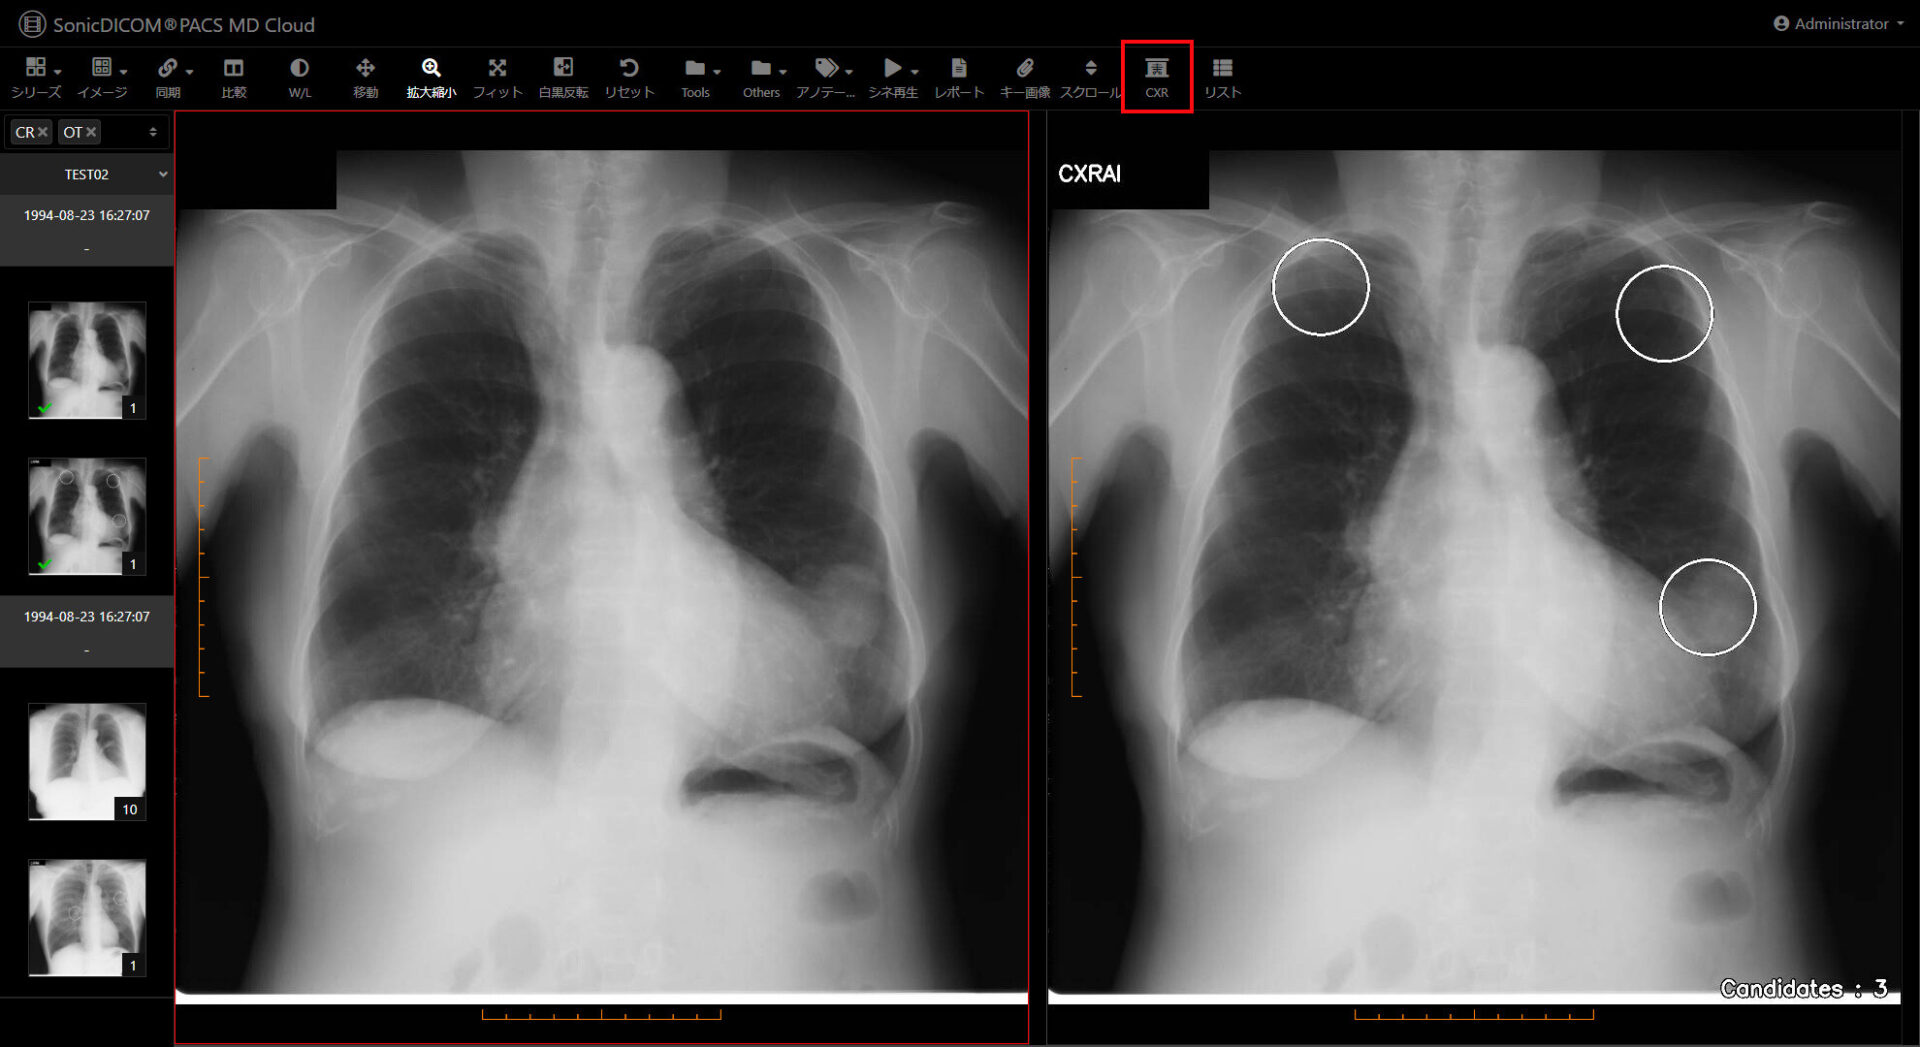

胸部正面画像を選択し、「CXRボタン」を押すだけでAIの解析結果が表示されます。

一般撮影装置またはPACS等のサーバーから胸部正面画像データを受信し、AI解析結果をPACSに送信します。

結果の表示方法

指摘箇所を”〇”で表示

指摘数を右下に表示